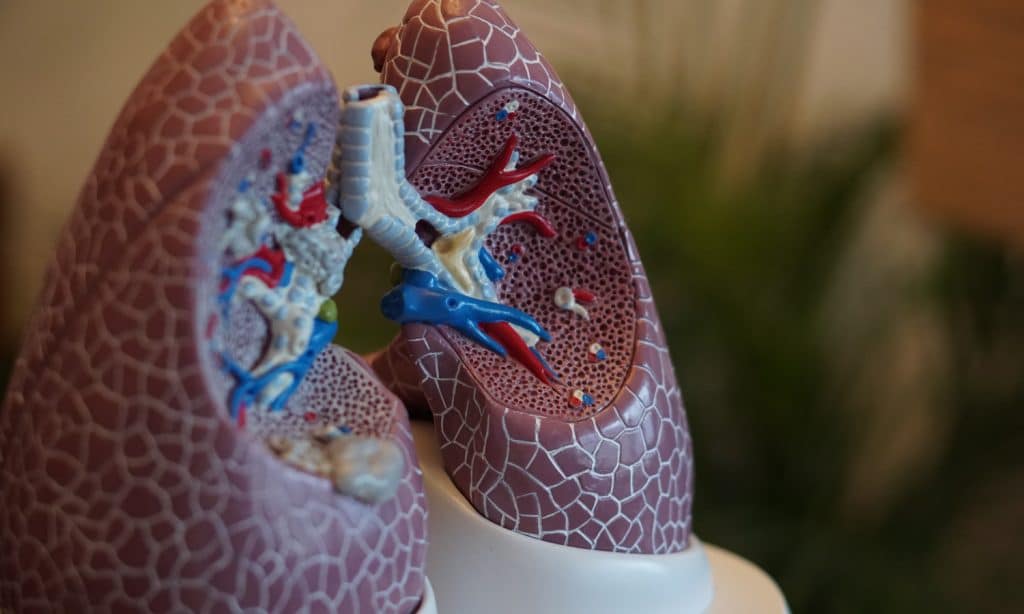

Lung health experts still don’t recommend inhaling any combustible material like tobacco or marijuana, due to the inflammation caused in your airways. However, cannabis has emerged as an unlikely candidate in preventing and treating COVID-19 symptoms.

Researchers at the University of Nebraska and the Texas Biomedical Research Institute now believe CBD could reduce the lethal lung inflammation caused by COVID-19. In a peer-reviewed article published in this month’s issue of Brain, Behavior, and Immunity, the researchers called for more studies into cannabinoids for their anti-viral and anti-inflammatory capabilities to combat the coronavirus.

“Acute infection is associated with a cytokine superstorm, which contributes to the symptoms of fever, cough, muscle pain,” researchers wrote. In severe cases, lung inflammation could lead to pneumonia, making it difficult to breathe for patients who already have weakened immune systems.